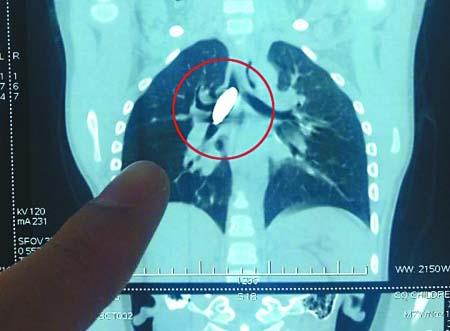

照片显示磁铁堵住了明明的气管(画圈处) 通讯员 刘雪潇 记者 张路桥 摄

儿童医院胸心外科安永教授说,明明当晚凌晨1点多钟被送来时,脸色很不好,照片显示磁铁堵在了气管下段及右侧主气管,造成气管下段及右侧主气管完全堵塞,患儿只能靠左侧气管通气,情况十分危险。由于磁铁体积太大,并且表面太过光滑,用传统方法难以取出,只能切开气管,如果气管切管都无法取出,就只能开胸了,那样的话,很有可能会造成肺部损伤。